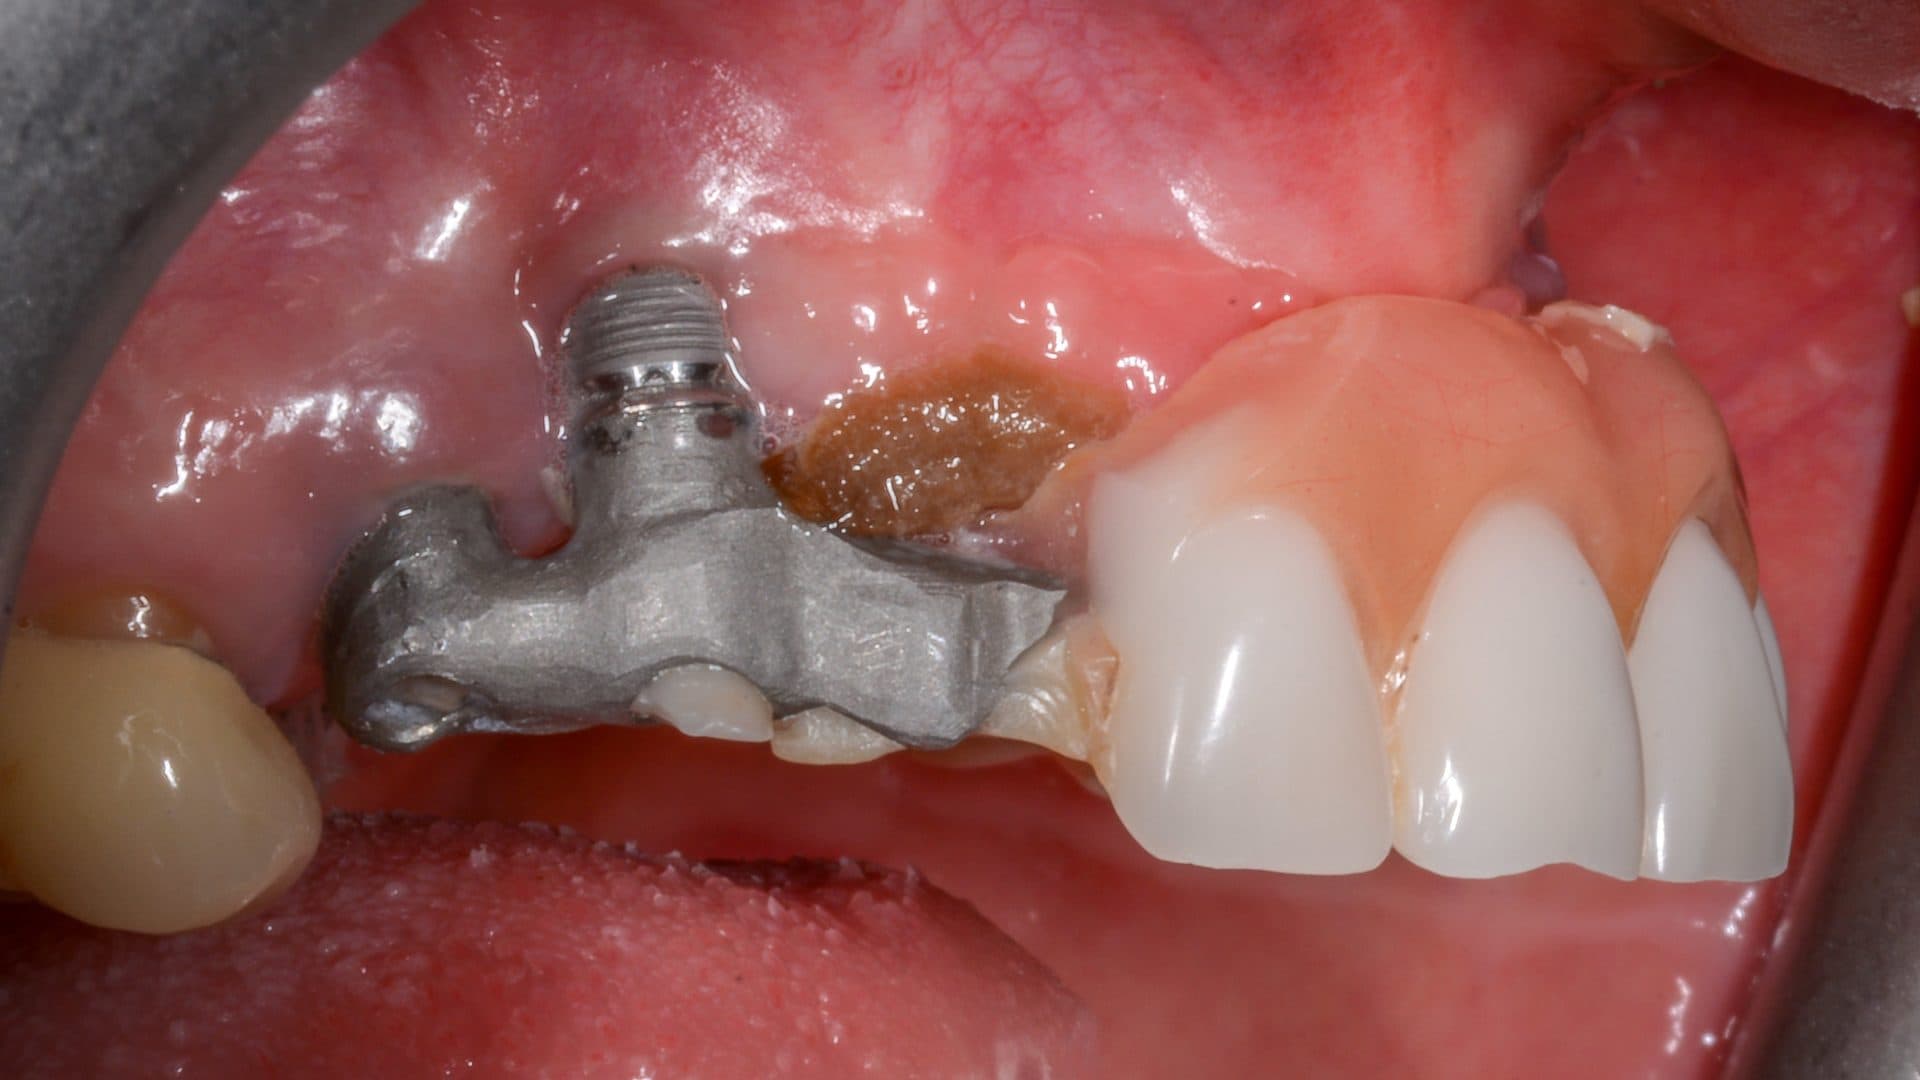

i. Even spread of the implants and flat and uniform under-surface/interface between the prosthesis and the natural gums. A deviation from this will affect the cleanability of the prosthesis, food entrapment and smell (See pictures);

Examples Of Poor Standards